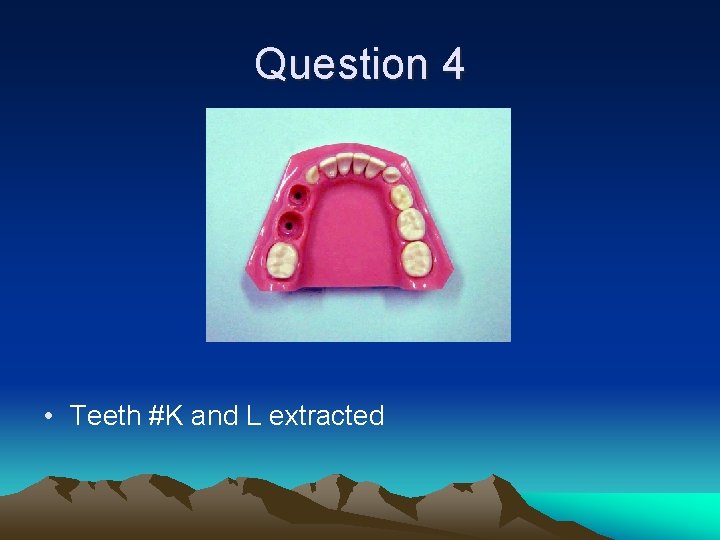

Question 4 • Which teeth were extracted/ • What is the appropriate space maintainer?

Question 4 • Teeth #K and L extracted